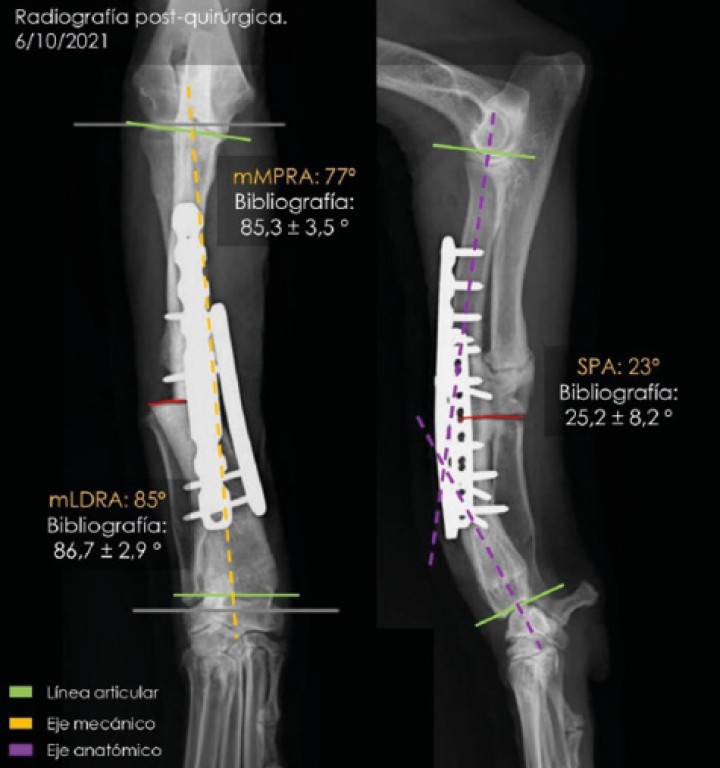

Después de la cirugía se analizaron las radiografías postoperatorias, realizándose las mismas mediciones que en la planificación, y observándose cómo los valores obtenidos tras la cirugía se correspondían con los valores planificados (Fig. 5). Se colocó un vendaje postoperatorio sencillo durante 14 días, para evitar la manipulación del área quirúrgica por parte de la paciente, lo que facilitó una cicatrización correcta de la herida y una buena recuperación del animal, que comenzó a caminar con normalidad a los pocos días de la intervención (Fig. 6).

Proyecciones radiográficas craneocaudal y mediolateral posquirúrgicas. Las radiografías muestran el resultado tras la cirugía.

Figura 5